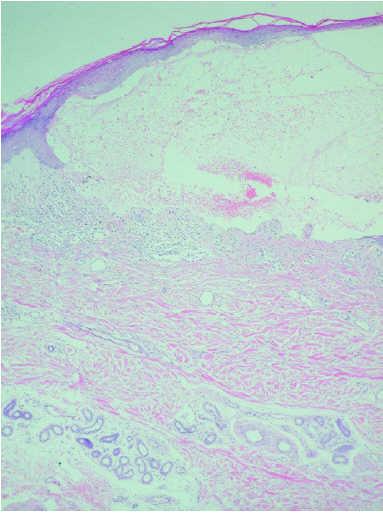

Se realizaron dos biopsias cutáneas; una de dorso de dedo de la mano (fig. 3), que mostró una prominente hiperqueratosis y acantosis, con focos de paraqueratosis e hipogranulosis, algunas áreas de exocitosis y espongiosis, queratinocitos necróticos e infiltrado linfocítico perivascular. La segunda fue tomada de una lesión ampollosa localizada en la superficie de una placa eritematoedematosa del dorso de la rodilla. Su estudio histopatológico (fig. 4) mostraba un despegamiento subepidérmico con un infiltrado inflamatorio superficial de linfocitos, neutrófilos y eosinófilos, así como dermatitis de interfase con degeneración vacuolar de la capa basal. La inmunofluorescencia directa (IFD) de la piel perilesional de la segunda biopsia demostró la existencia de depósitos granulares de inmunoglobulinas (IgM, IgA) y C3 en la membrana basal (fig. 5).

Fig. 4.--Ampolla subepidérmica con infiltrado inflamatorio superficial de linfocitos, eosinófilos y neutrófilos. (Hematoxilina-eosina, ×40.)